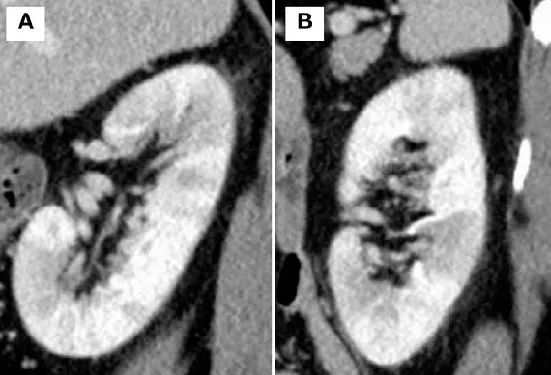

Doença renal policística e Transplante de Fígado: o nefrologista deve ficar atento a indicação

Doença renal policística e Transplante de Fígado: o nefrologista deve ficar atento a indicaçãoÉ comum que o nefrologista se depare com pacientes com DRPAD e acometimento hepático importante? confere esse post sobre os critérios que devemos levar em consideração para encaminhar o paciente para avaliação do transplante de fígado!